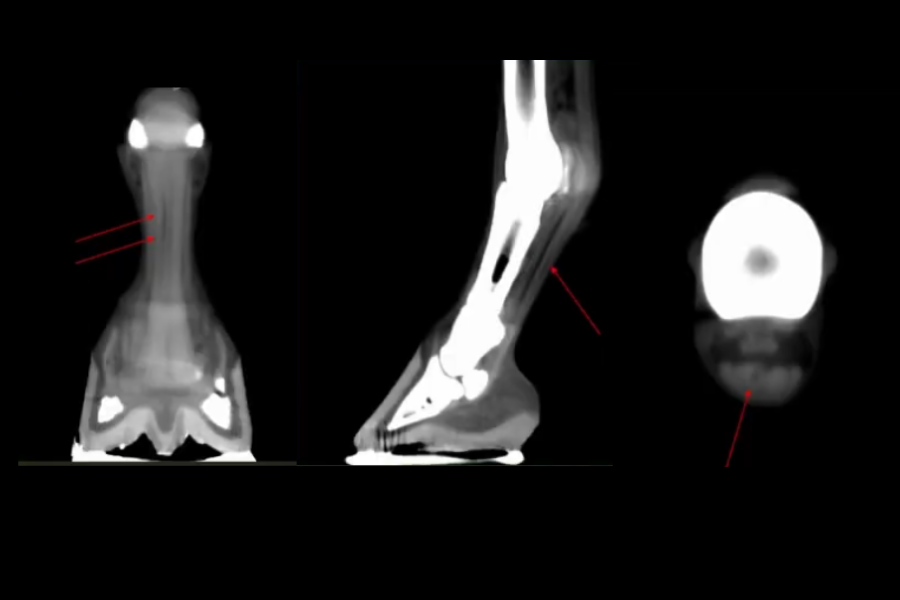

Computed Tomography (CT) is a noninvasive cross-sectional imaging modality that produces a 3D view of part of the body. During a scan, an x-ray beam rotates around the body part, capturing images in slices that a computer pieces together to create a detailed picture.

• Standing CT is the best way to get diagnostic quality images of an injury to your horses head, neck or lower limbs. The procedure is much faster and produces higher quality images than traditional x-rays and does not require general anesthesia, which is required for conventional CT.

• Limb scanning: If your horse is scheduled for a limb scan, a facility handler will first bring your horse from the stalls to the Standing CT imaging room. The handler will then lead your horse onto the Equina imaging platform using a lead rope. To image the limbs, either the two front limbs, or the two rear limbs are positioned within the opening of the CT gantry, which sits below the ground. Before scanning, your horse will be sedated to minimize movement during the scan. The operator then positions the CT gantry and collects the images moving the CT gantry up and down the limbs. Scan time is generally only about 20 seconds. After scanning, your horse will be led back to the stalls to recover from sedation.

• Lameness and musculoskeletal issues are common in horses and can be hard to diagnose. Because of the high quality of Equina images, it is particularly helpful in finding the specific causes of lameness and other lower limb problems.